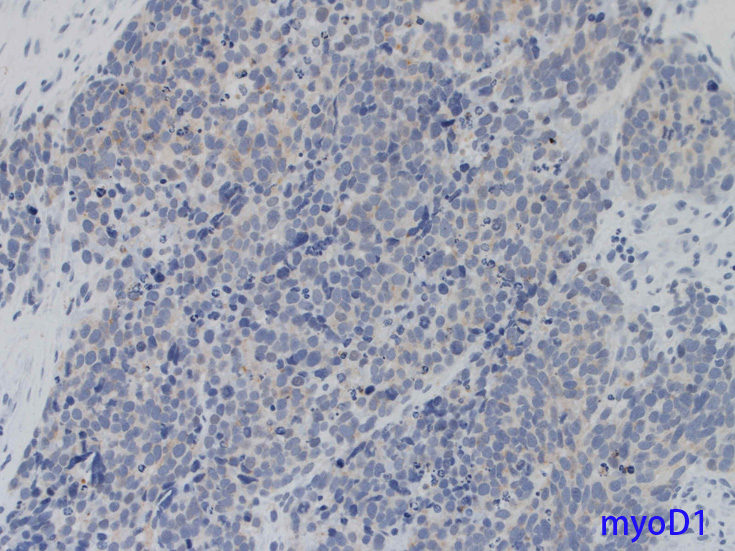

Desmin, 筋特異的アクチン(HHF-35), myoglobin, MyoD1, myoegeninなどの筋マーカはARMSでよく染色されるがES/PNETでは陰性である。

筋形成過程は多潜能未熟間葉系細胞の骨格筋へのcommitmentとdifferentiationからなりMyoD遺伝子ファミリーにより制御されている。このファミリーにはMyoD1/myf-3, myogenin/myf-4, myf-5, MRF-4遺伝子などが含まれ, 筋特異遺伝子上エンハンサー領域に結合し発現誘導の転写因子として働くDNA結合蛋白をコードしている。

骨格筋ではこれらの遺伝子発現は胚形成期に限られるためMyoDやmyogenin抗体は細胞系列の同定や他に分化や特徴のない肉腫においてrhabdomyosarcoma診断確定の目的で使われてきた。

免疫染色 筋マーカ, 神経内分泌マーカほか;本例では神経内分泌マーカがすべて陽性になっている.

rhabdomyosarcomaではCKなど上皮マーカ-、神経内分泌マーカ-などが発現することがしばしばあり誤診しないことが重要。